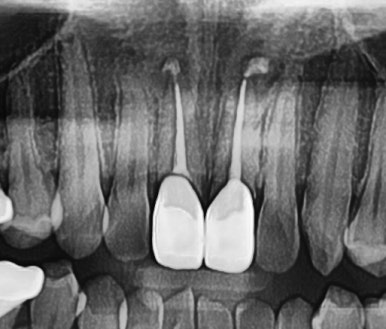

📸 케이스 3: #26 Re-Endo

- 1년간 지속된 이물감, 교합 조정에도 개선 없음

- GP Cone이 끝까지 도달하지 않아 재신경치료 시행

- 염증은 없었으나 증상 호전 목적

✅ 치료 후 통증 완화